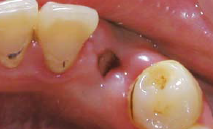

女性,22 岁, 现病史:外伤致33 脱落1 周后求诊,要求种植修复 既往史:无特殊

左下3缺失,牙龈略红肿,近远中距离可,对颌无伸长 X线示牙槽窝内空虚